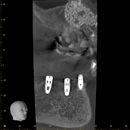

サイナスリフト実施7ヶ月後、インプラント埋入を行いました。

上顎3本(ダミー2歯のブリッジ形態)と下顎2本(ダミー1歯のブリッジ形態)埋入して、上顎サイナスリフトを行う場合は、以下のとおりです。

| 上顎 | インプラント275,000円×3+ダミー55,000円×2+サイナスリフト165,000円+手術代132,000円(税込) |

| 下顎 | インプラント275,000円×2+ダミー55,000円+手術代132,000円(税込) |